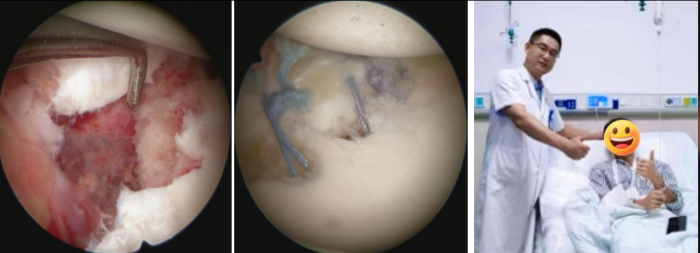

微创关节镜技术精准修复“破碎的关节边缘”

考虑到患者年轻且有强烈的运动需求,运动医学科团队为他实施了关节镜下微创修复手术。通过三个几毫米的小切口,精准地将撕脱的骨折块和盂唇组织复位到原位,并将它们牢固地重新固定在了肩胛盂上,恢复了肩关节稳定性结构,患者术后恢复良好,现已进入个性化的康复阶段。

关节镜下微创修复手术,患者术后恢复良好